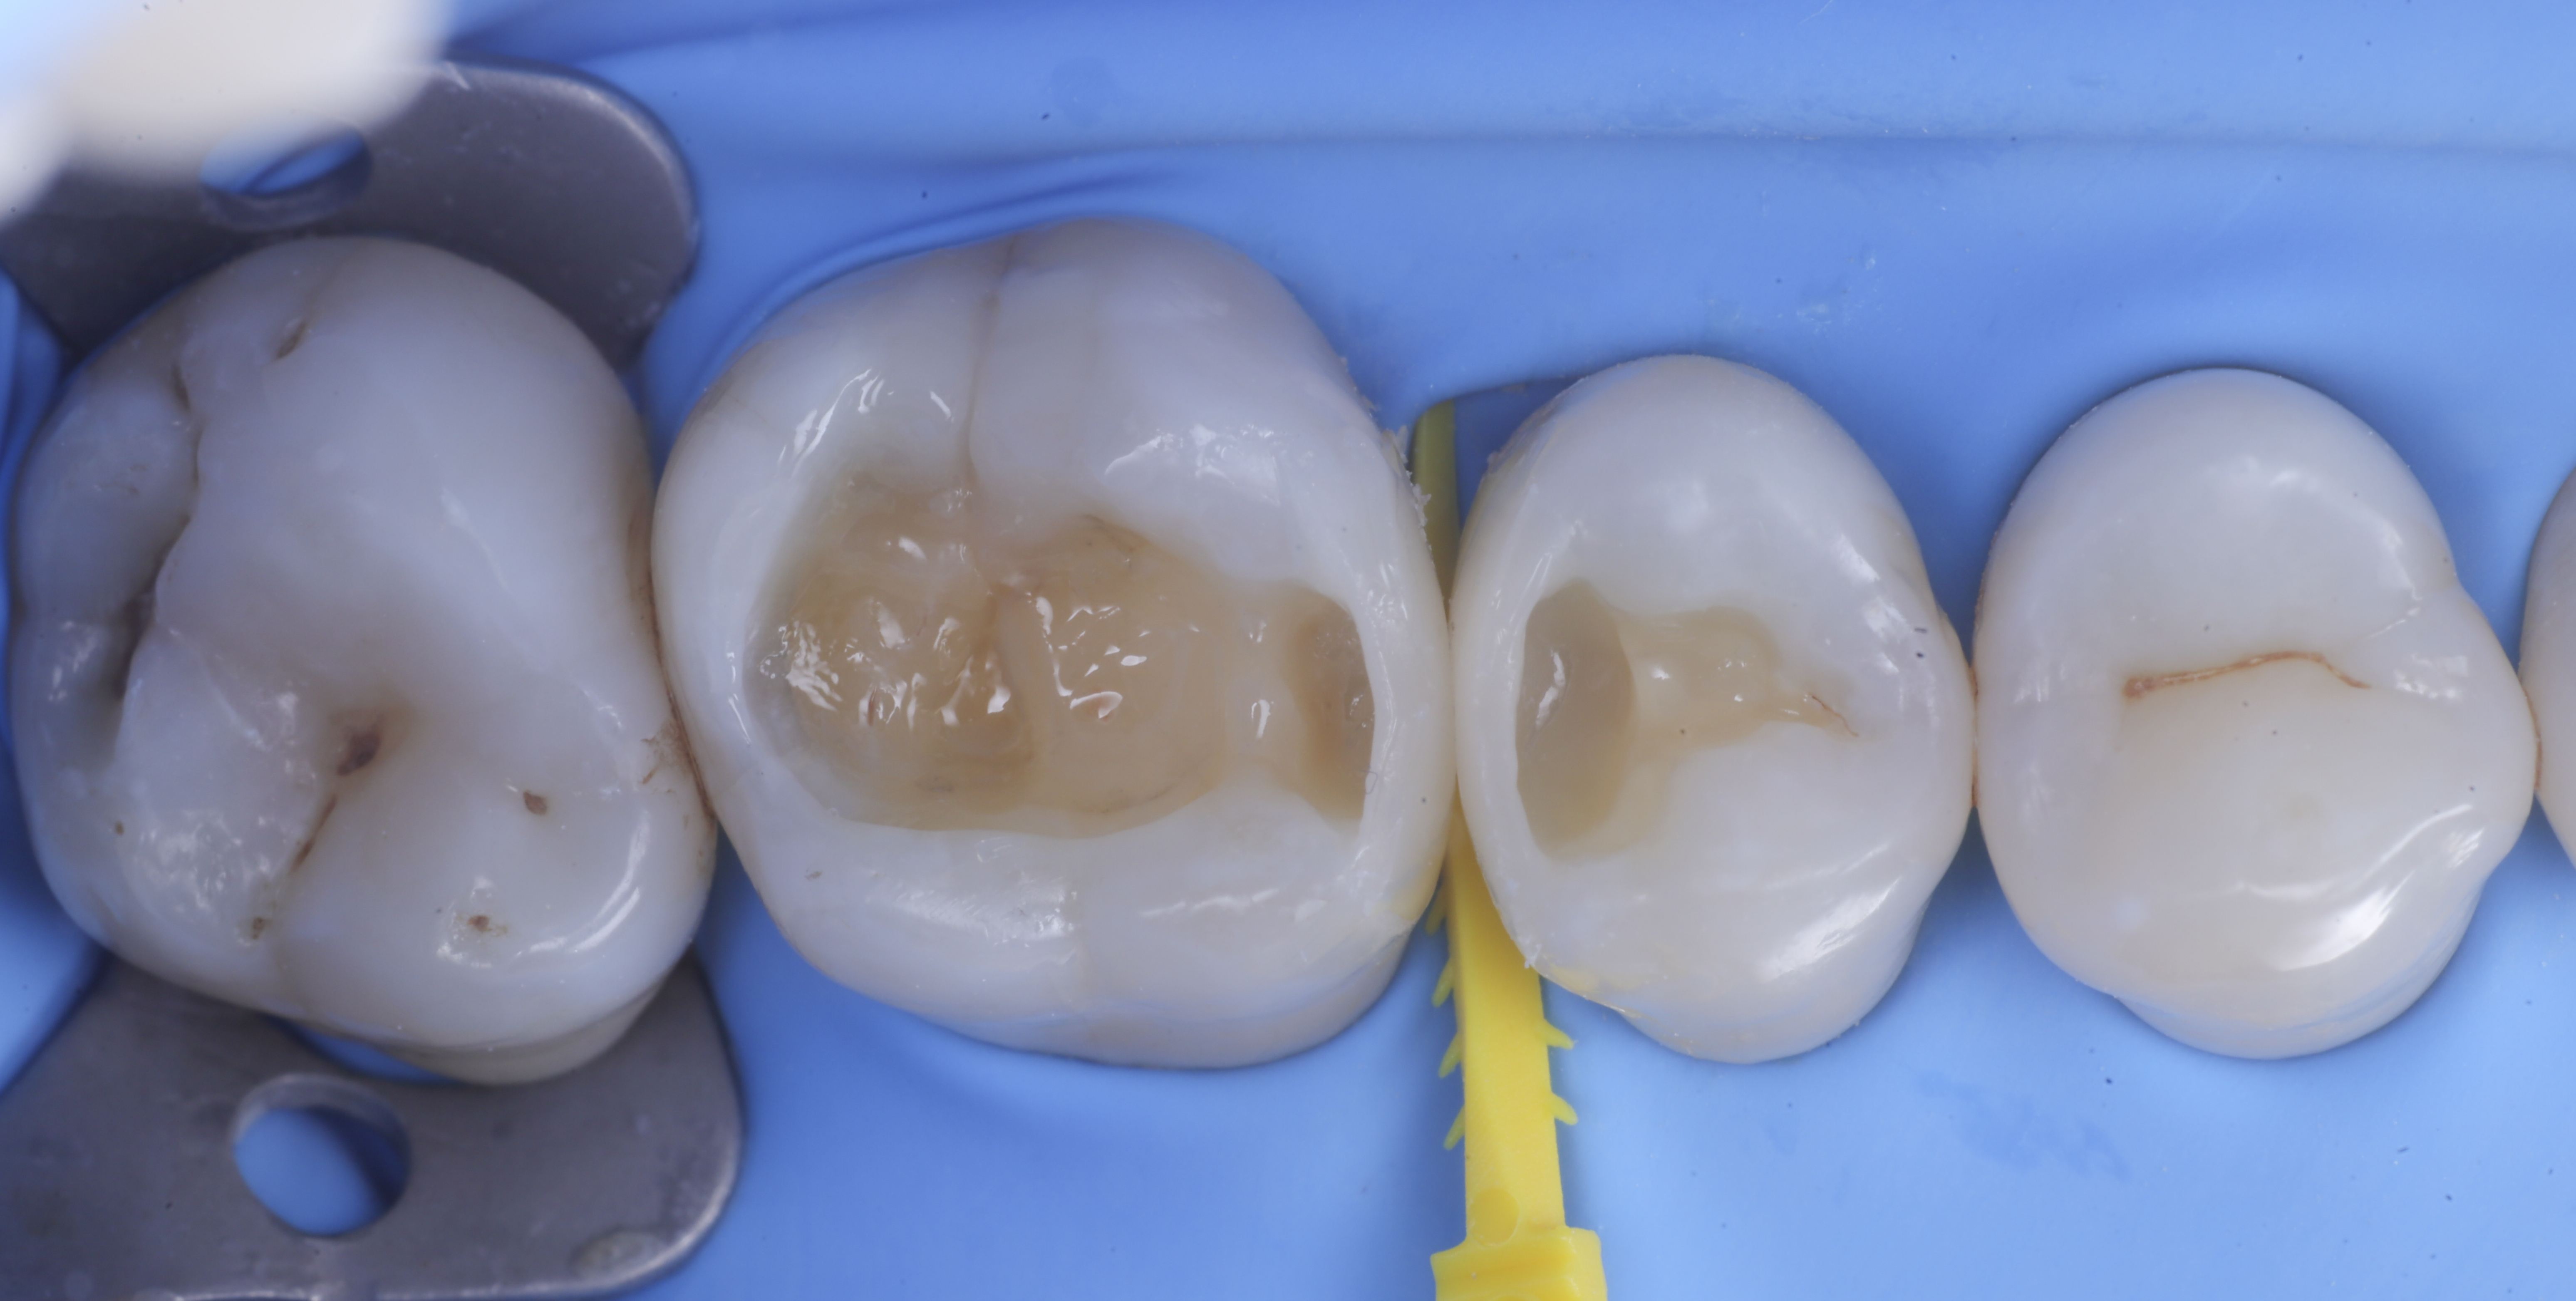

foto 8 Modellazione ed aspetto occlusale

foto 9 Modellazione ed aspetto vestibolare

foto 10 Modellazione ed aspetto palatino

foto 11 Restauri ultimati sotto controllo occlusale